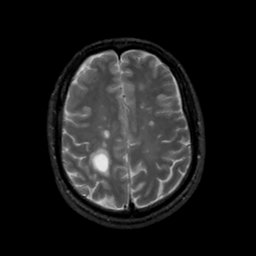

MR Study #6, March 17, 1991 -- Slice #36